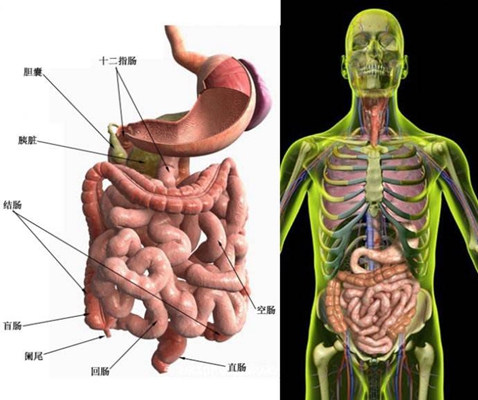

盲腸炎圖片

盲腸的位置 (50)

盲腸的位置 (6)

盲腸的位置 (7)

盲腸的位置 (8)

盲腸的位置 (9)

盲腸的位置 (46)

盲腸的位置 (47)

盲腸的位置 (48)

盲腸的位置 (49)

盲腸的位置 (5)